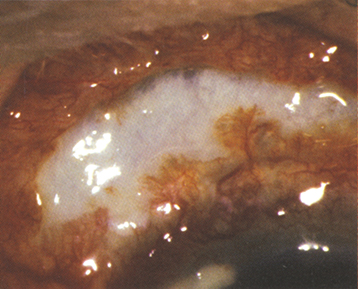

3. Necrotizing anterior scleritis with inflammation (see Figure 5.7.2): Extreme pain. The sclera becomes transparent (choroidal pigment visible) because of necrosis. High association with systemic inflammatory diseases.

Figure 5.7.2: Necrotizing scleritis with thin, bluish sclera.

Rapuano9781975243722-ch005_f016.jpg